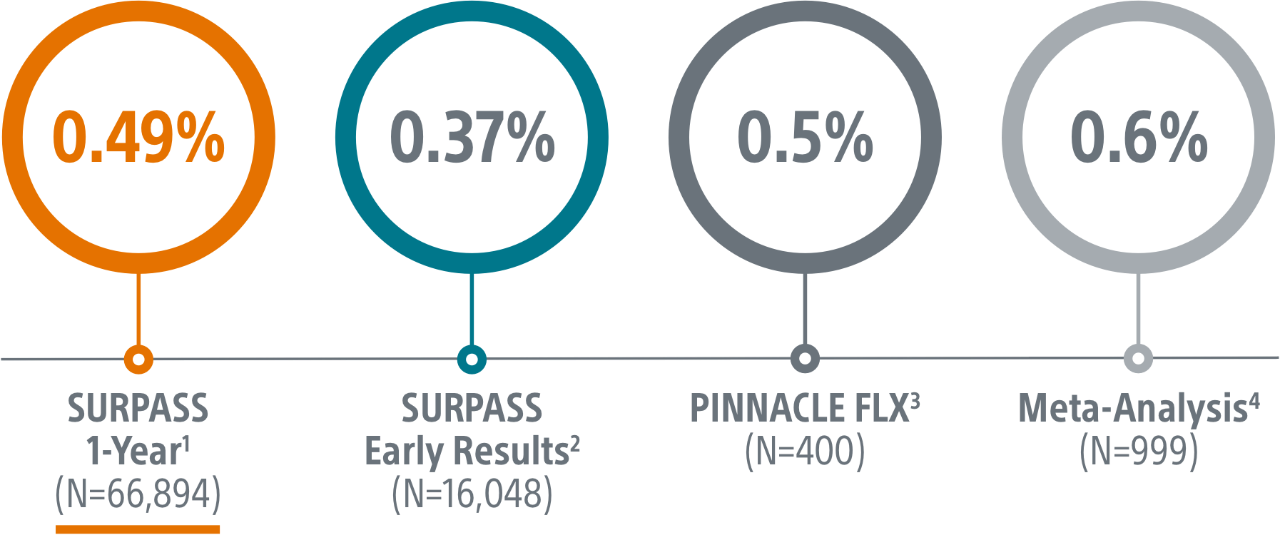

Built off the most studied, most implanted LAAC device in the world, WATCHMAN FLX is a proven alternative to long-term OAC therapy1 for stroke risk reduction in patients with non-valvular atrial fibrillation.

SURPASS demonstrated 0.37% major procedural adverse event rate within 7 days or hospital discharge in 16,048 commercial patients and confirmed the trusted safety profile of WATCHMAN FLX in real-world clinical practice setting.

The SURPASS Data reinforces the excellent safety profile WATCHMAN FLX demonstrated in the PINNACLE FLX Trial, with the largest (n=16,048) real-world WATCHMAN FLX patients studied to date.

Surpass 1 Year Results

- The objective of this SURPASS analysis is to assess long term safety and efficacy outcomes at one year with WATCHMAN FLX in a routine, real-world setting.

- This analysis includes the largest commercial WATCHMAN FLX patient population to date, with 66,894 patients implanted between August 5, 2020 and March 31, 2022.

2. Kapadia, CRT 2022.

3. Kar, Circulation 2021.

4. Della Rocca et al. Heart Rhythm 2022.

5. Ellis, Heart Rhythm, 2021.

6. Korsholm, WM FLX First Experience, JACC, 2020.

7. Bergmann, Alster Registry, Presented ePCR 2021.

8. Betts, EHRA 2022.

9. Galea, SWISS APERO Trial, Cirulation, 2021.

10. Freeman, HRS 2022.